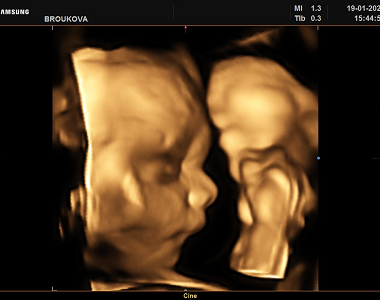

Petra si ve 26. TT ze 4D ultrazvuku přivezla krásné fotky i video

Petra byla v posledním týdnu hned na dvou vyšetřeních. Na klasické kontrole se Ondráškovi moc fotit nechtělo, ale 4D ultrazvuk si zřejmě užil, akční b...